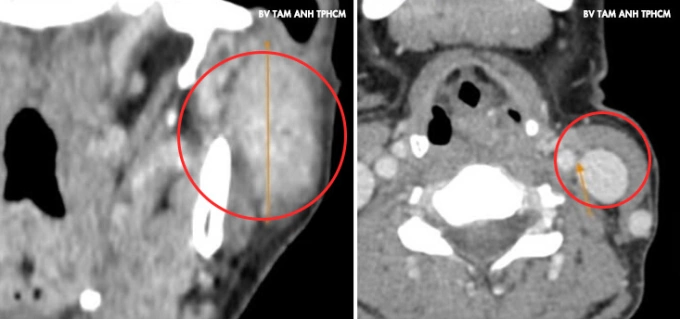

Ảnh chụp CT ghi nhận khối u lớn vùng mang tai trái của chị Dương. Ảnh: Bệnh viện Đa khoa Tâm Anh

U xuất hiện ở góc hàm mang tai trái của chị Dương một năm trước,nhỏ và không đau,không liệt mặt,khác với đặc điểm chung của loại u này là thường phát triển rất nhanh gây đau và liệt dây thần kinh mặt. Gần đây,u sưng hơn khiến mặt mất cân đối,chị đến Phòng khám Đa khoa Tâm Anh Quận 7 kiểm tra. Kết quả chụp CT và siêu âm ghi nhận khối u dài hơn 4 cm chiếm gần hết mô tuyến mang tai trái,phát triển vào trong xâm lấn dây thần kinh 7 và tĩnh mạch sau hàm. Cạnh trước khối u có hạch gần 1 cm và hai hạch hơn 1 cm vùng cổ. Kết quả sinh thiết chọc hút tế bào kim nhỏ là u tuyến mang tai hóa bọc,chưa xác định ung thư.